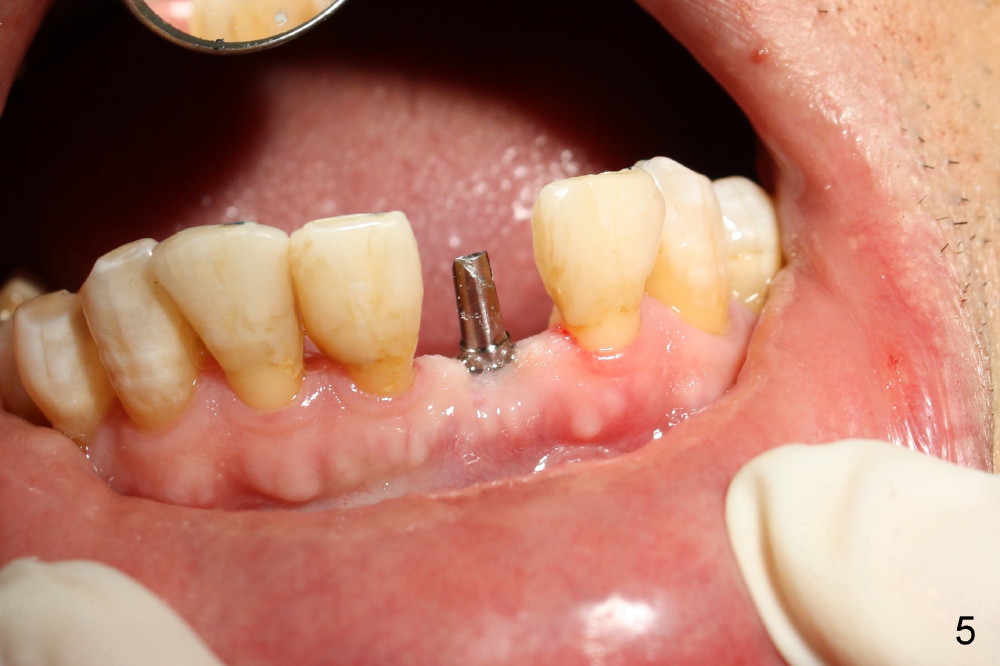

A 3x17 mm one piece implant is planned.  Osteotomy is created by a 1.5 mm pilot drill at the depth of 14 mm without incision (Fig.2); it is close to a neighboring incisor.  The trajectory of the osteotomy is intended to be changed (Fig.3 red) without success (white, 17 mm deep).  With measurement and calculation, the 3x17 mm implant is not expected to touch the root of the adjoining tooth.  In fact it is fine with insertion torque between 50-60 Ncm (Fig.4).  Without incision, the papillae appear to form immediately following implantation (Fig.5).  With adjustment of the abutment (Fig.6), an immediate provisional is fabricated (Fig.7).